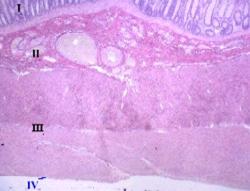

На зображенні представлений загальний вигляд слизової

оболонки у відділах травної трубки: стравоході (А), шлунку (Б), тонкій кишці

(В) та у товстій кишці (Г). На будь-якому рівні травна трубка має у своїй

стінці слизову оболонку (І), підслизову основу (ІІ), м’язову оболонку (ІІІ) та

зовнішню серозну (ІV). Слизова оболонка може утворювати такі структури, як

складки, ямки (1), крипти (2) і ворсинки (1). Отже, дамо характеристику окремих

шарів травної трубки.